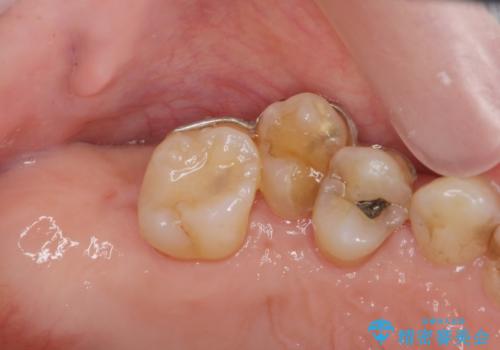

部分矯正を含む 歯周病治療 (再生治療・歯周ポケット除去・MTM・連結補綴)

- 歯のぐらつき、歯周病の検査を希望され来院されました。

検査の結果、強い歯ぎしりによる歯の周囲の骨の吸収が認められたため歯槽骨の再生・歯周ポケットの除去・力に対抗する連結補綴・補綴前処置としての小矯正を計画します。